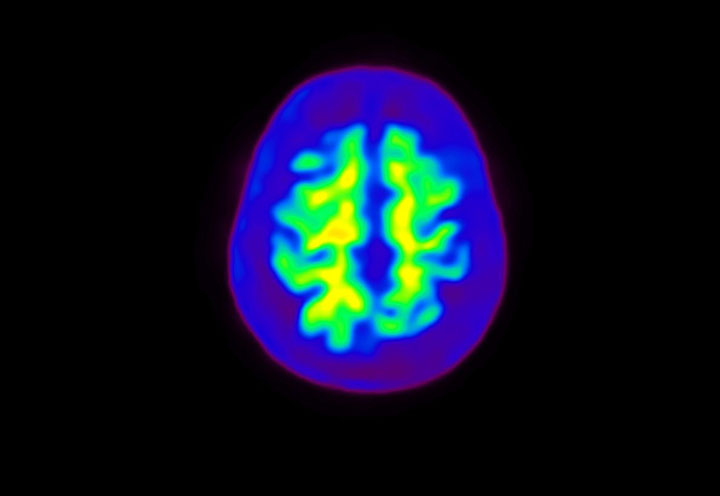

Head / Case4 : Amyloid

Courtesy : Kindai University Hospital

- Imaging protocol

- Injected dose: 3.21 MBq/kg, 18F-Flutemetamol

- Uptake time: 100 minutes

- Scan time: 20 minutes